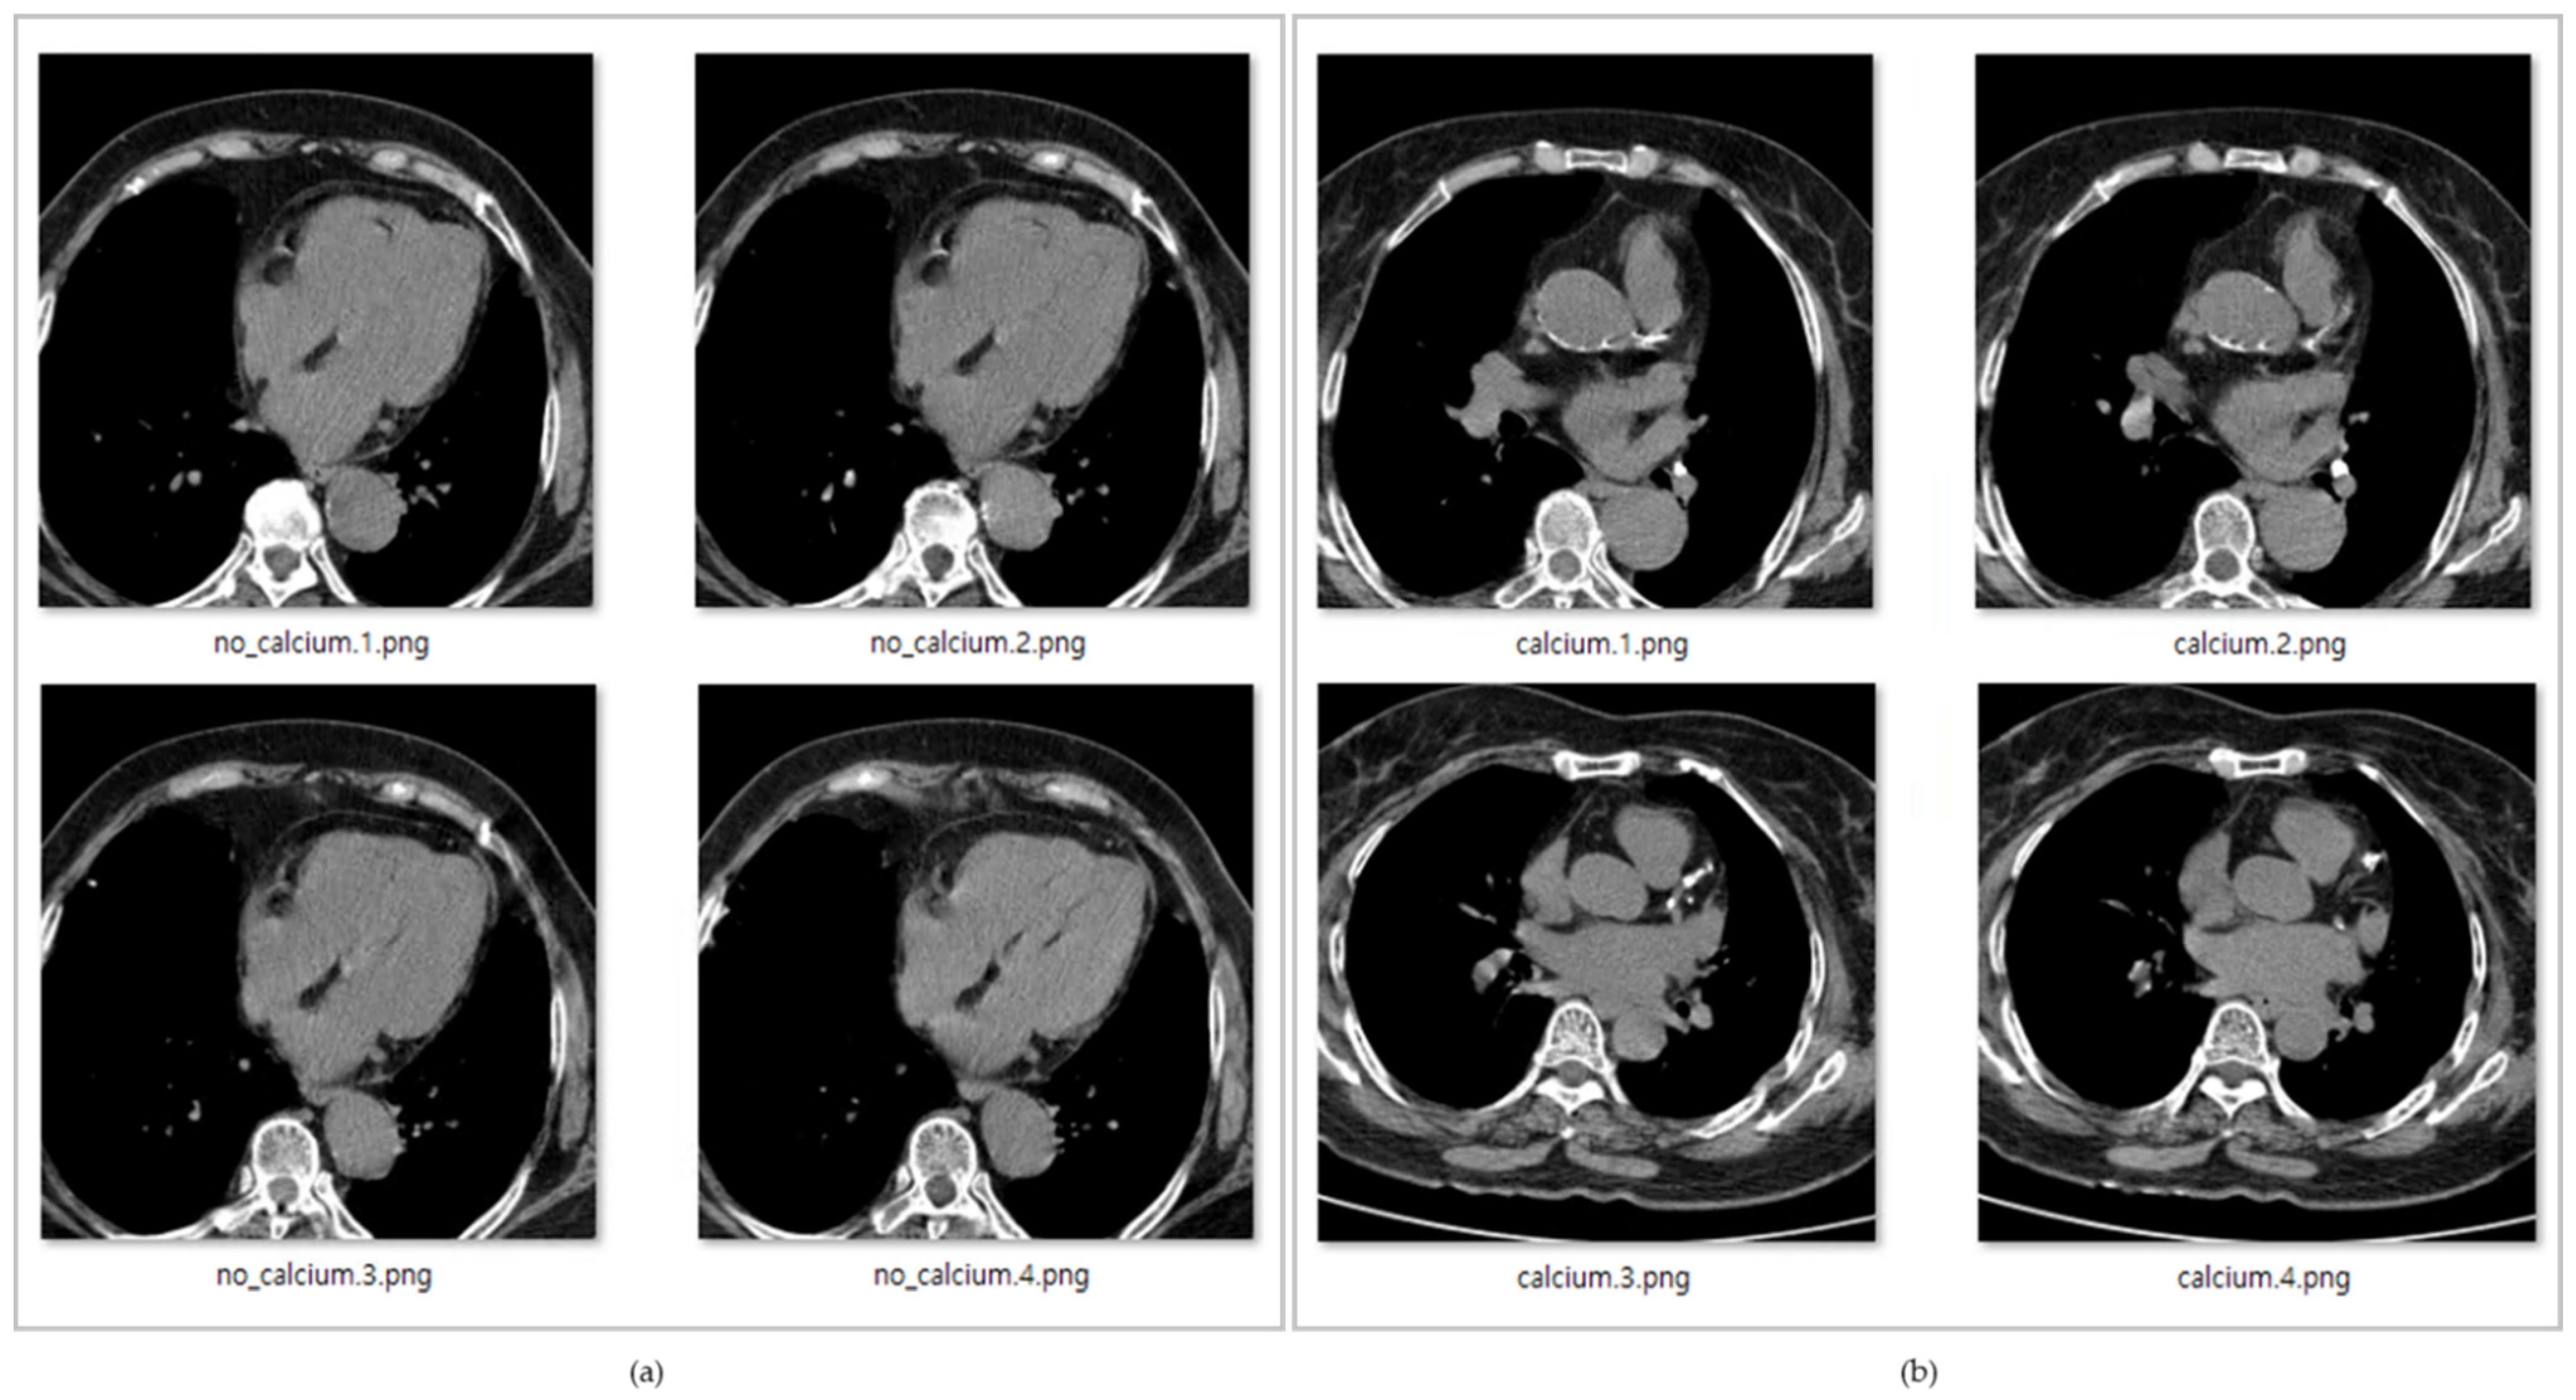

In Figure 5, the data with title beginning with ‘calcium’ is the data with calcium in the coronary arteries, while the data with title starting with ‘no_calcium’ is the normal data, in which calcification in the coronary arteries has not progressed.

Figure 5.

(a) Original coronary artery calcium score CT image without calcification, (b) Original coronary artery calcium score CT image with calcification.